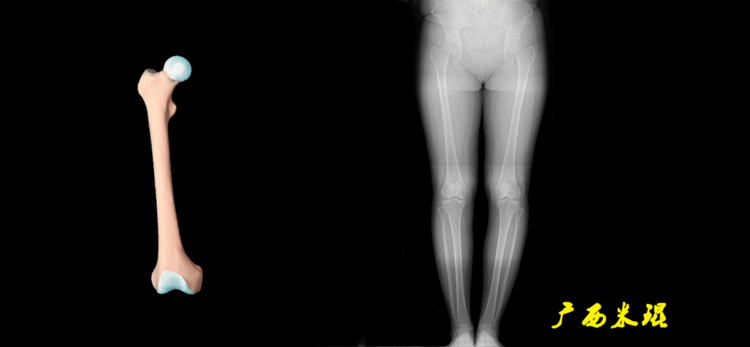

下肢力线及相关角度测量的前提是必须拍摄标准的站立位也就是负重位的下肢全长片。目前这样的照片都是放射科的技师在电脑上拼接出来的,大部分医院的DR都能够做到这一点。

患者直立于摄影架上,后背贴近摄影架,双手自然下垂,膝关节尽量伸直,足部与双肩同宽,要求投照时双髌骨朝正前方,通常患者双足尖应平行向前即可。

提醒一下大家,拍摄过程中应避免下肢的外旋和内旋。如果有一侧肢体短缩时,投照应当用脚垫垫高短缩肢体,使骨盆保持水平,这样下肢短缩测量才精确。如果有肢体旋转畸形时,还是以髌骨朝前为标准,虽然此时双足可能不能保持平行。

下肢全长片的基本要求

无论如何,拍摄出来的下肢全长片必须包含髋关节中心、膝关节中心及踝关节中心,否则对临床是无用的。有了一张下肢的全长照片,我们需要确定下肢关节的中心点,通过中心点画出下肢的各种轴线,然后利用轴线与关节线的相交得出各种所需要的角度。